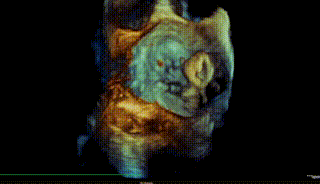

图8-10. 由于反流偏3区,需在MultiVue指导下进行瓣叶捕获夹合,先植入偏3区的夹子后,再次跨瓣植入偏2区的第二枚夹子,二夹收紧后即刻可见反流降至轻度

图11. 二夹解离后3D心房观